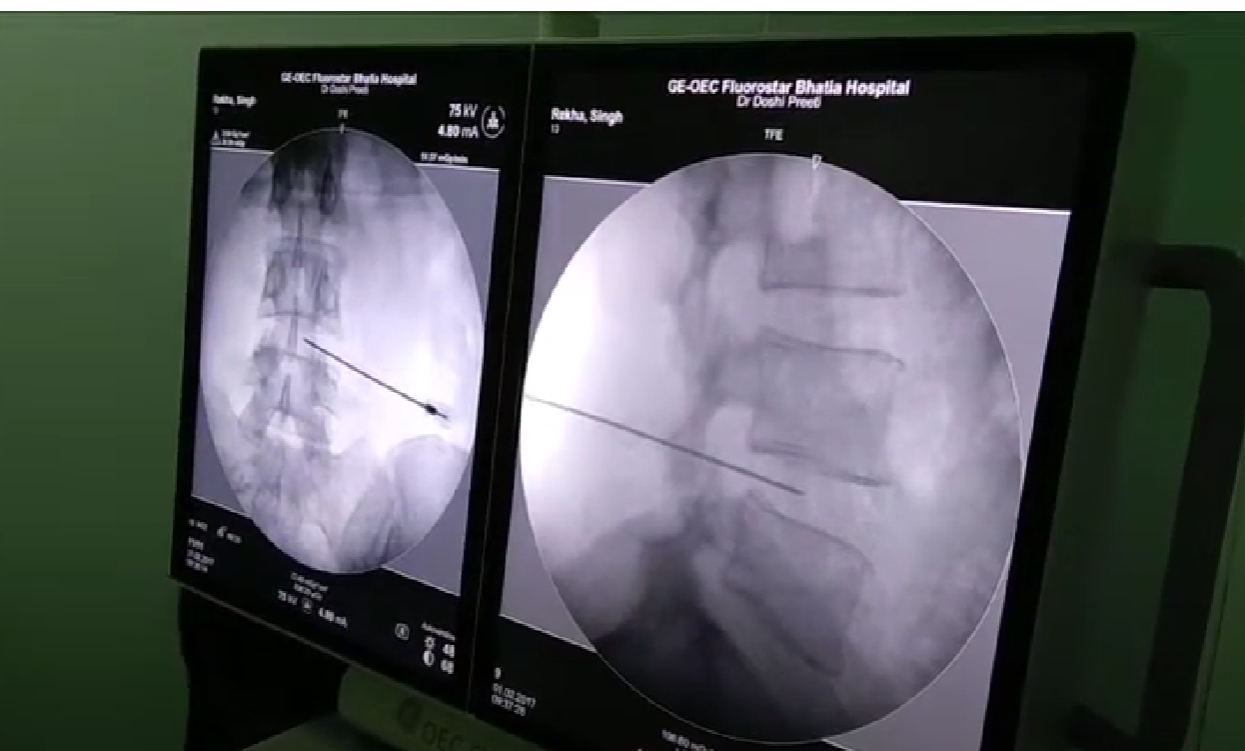

PLDD uses laser energy to reduce the pressure within a herniated disc, relieving pain. The procedure involves inserting a thin needle into the affected disc under local anesthesia and imaging guidance, then delivering laser energy through the fiber to vaporize a small portion of the disc material, reducing disc pressure.